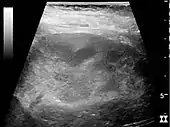

Хронический пиелонефрит с уменьшением размера почек и очаговым истончением кортикального слоя. Измерение длины почек на ультразвуковом изображении показано знаком «+» и пунктирной линией.[4]

- Content initially copied from: Hansen, Kristoffer; Nielsen, Michael; Ewertsen, Caroline (2015). “Ultrasonography of the Kidney: A Pictorial Review”. Diagnostics. 6 (1): 2. DOI:10.3390/diagnostics6010002. ISSN 2075-4418. PMC 4808817. PMID 26838799. (CC-BY 4.0)